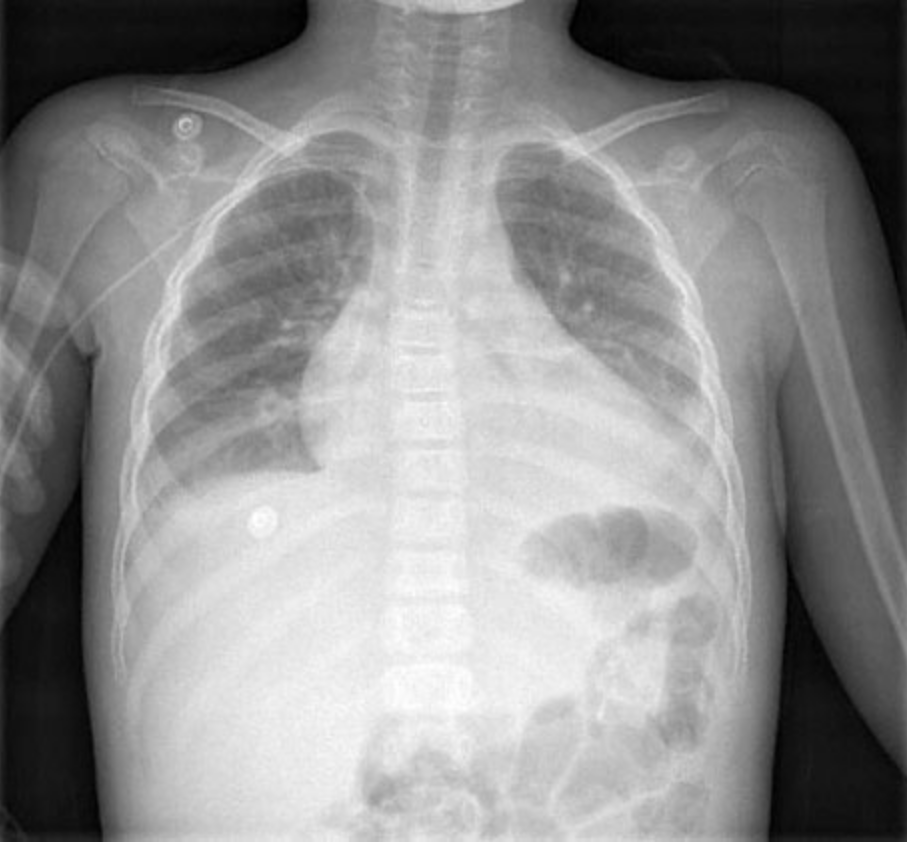

An 8-year-old African American girl with sickle cell disease is brought to the physician by her mother because of a 12-hour history of cough and difficulty breathing. Her medications are penicillin and folic acid. Her temperature is 39°C (102.2°F), pulse is 130/min, respirations are 40/min, and blood pressure is 105/60 mm Hg. Pulse oximetry on room air shows an oxygen saturation of 94%. On pulmonary examination, crackles are heard in the upper lobes. Breath sounds are decreased at the lung bases bilaterally. The remainder of the examination shows no abnormalities. An x-ray of the chest is shown. Which of the following is the most appropriate next step in diagnosis?